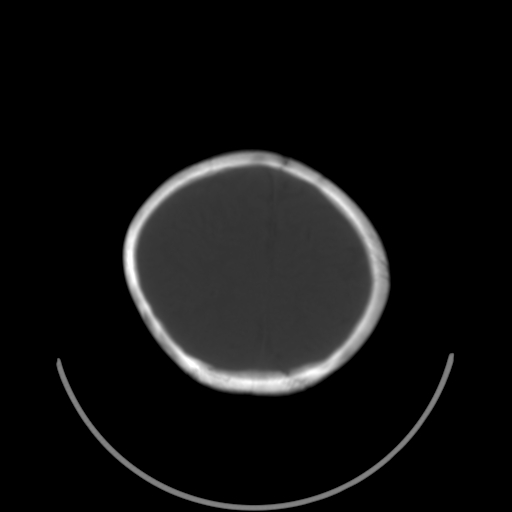

以下是引用深泽交通医院在2009-10-16 8:25:00的发言:[br]右眼环出血伴异物

以下是引用卜一在2009-10-16 15:01:00的发言:[br]右眼球挫裂伤伴异物!

以下是引用拾荒者在2009-10-17 18:38:00的发言:[br]鼻面部皮下积气,右侧睑缘及眼球壁高密度异物影,左侧眼球壁晶状体内侧缘处是圆形低密度影。低密度异物?应提请眼科医生注意。